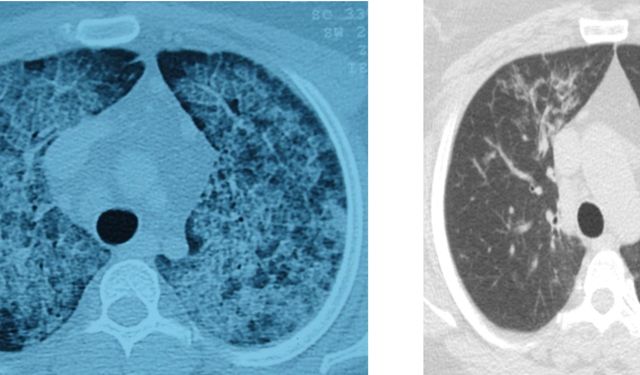

Akciğer yıkaması yöntemiyle hastalar yeniden rahat nefes alıyor

Sağlık